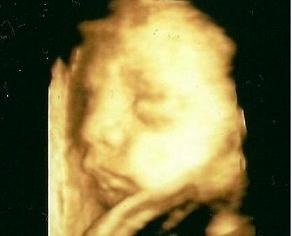

Nonó az elsőn,Bazsi a másodikon:

Kép Kép